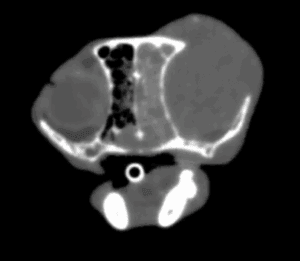

犬の副腎腫瘍は、大きく臨床症状を示す「機能性腫瘍」と、症状を示さず画像検査で偶発的に見つかる「副腎偶発腫」に分類されます。副腎は外側の皮質からコルチゾールなどのステロイドホルモンを、内側の髄質からカテコラミンと呼ばれるホ […]